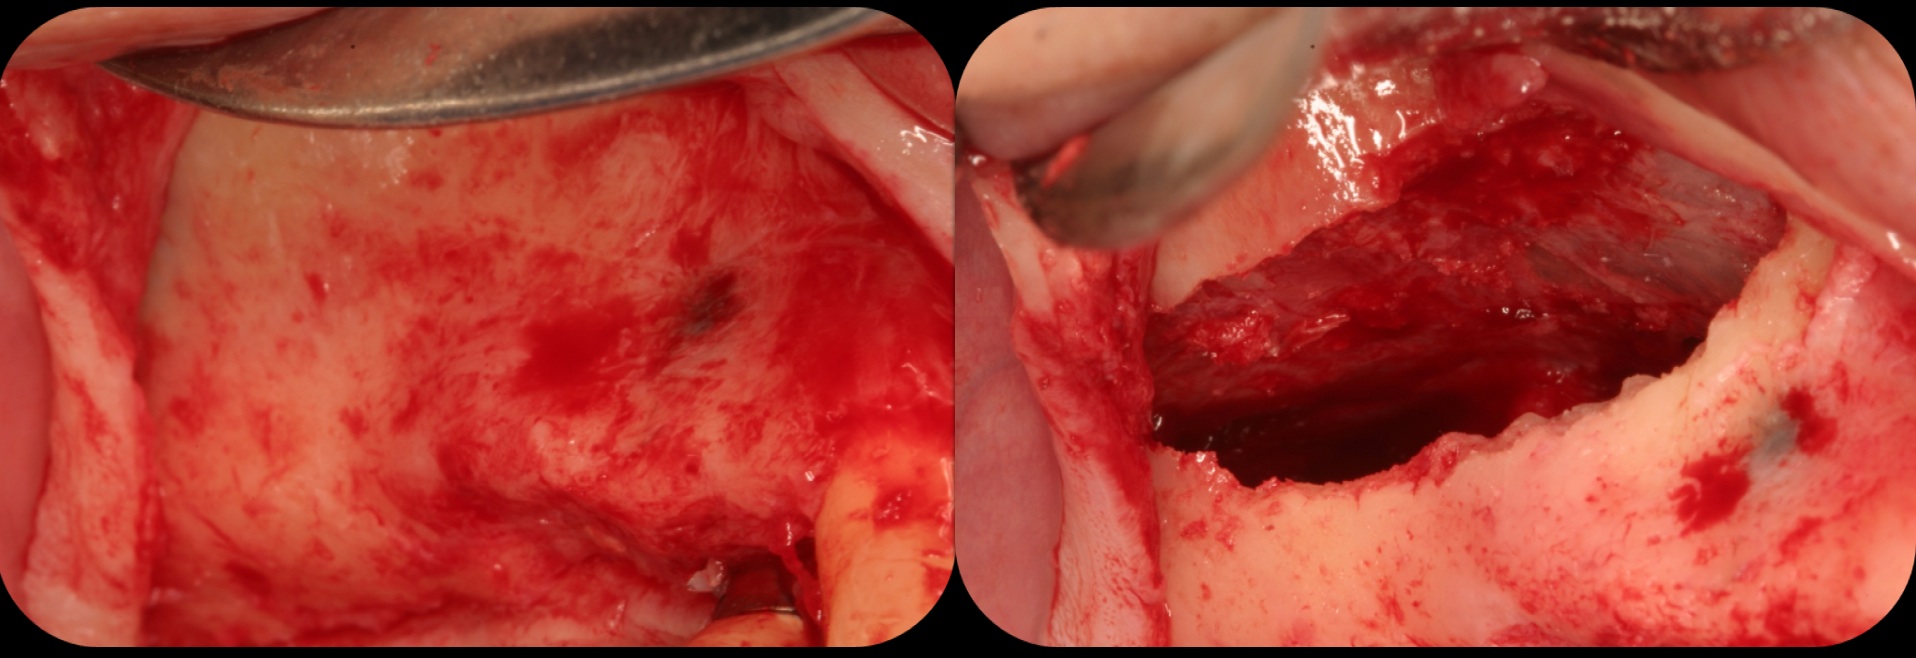

Then, too, are opportunities to prepare the site for regeneration by coupling therapies, applying an enamel matrix derivative, along with traditional bone grafts of demineralized freeze-dried bone allograft; potentially, gains in attachment with minimal probing depth and retained papilla may avoid the need for an implant (Figure 2 through Figure 7).

Severe periodontitis lesion.

Fig. 2

Facial bone loss and a mesial vertical defect.

Fig. 3